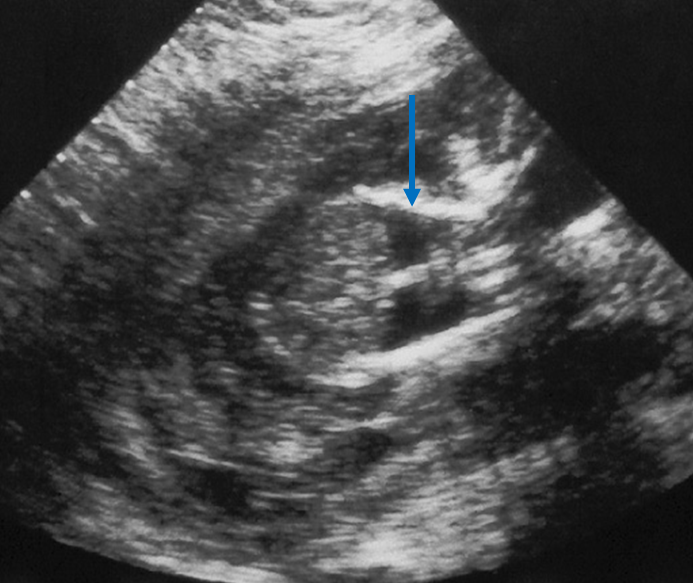

What view is this?

5 chamber view (used to recored aortic root, outflow, LVOT)

Crisscross view